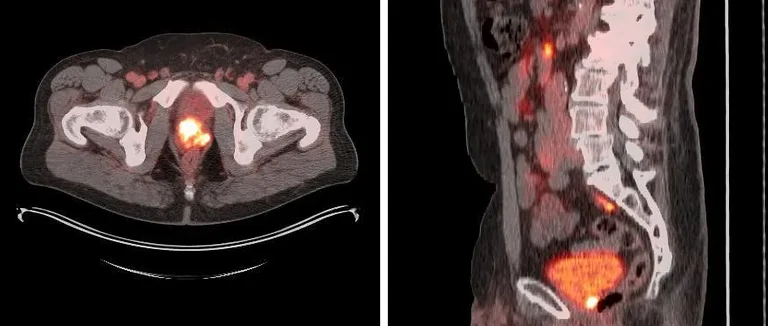

Le TEP-scan amyloïde est une méthode d'imagerie pour voir les protéines amyloïdes dans le cerveau. Il est très utile pour diagnostiquer la maladie d'Alzheimer. Cela aide à repérer les plaques amyloïdes, un signe clé de cette maladie.

On va voir comment ça marche et comment il diffère des autres méthodes d'imagerie du cerveau. Ce scan utilise un traceur radioactif qui s'attache aux dépôts amyloïdes. Ainsi, on peut voir ces dépôts grâce à la tomographie par émission de positons (TEP).

Le TEP-scan amyloïde est une façon d'imagerie qui montre les dépôts amyloïdes dans le cerveau. Il injecte un traceur radioactif qui s'attache aux plaques amyloïdes. Ce traceur émet des positons que le scanner TEP détecte, créant des images détaillées des dépôts amyloïdes.

Le TEP-scan amyloïde est unique car il détecte les dépôts amyloïdes. Il diffère de l'IRM et du scanner CT, qui montrent la structure du cerveau. Le TEP-scan amyloïde montre la présence et la distribution des plaques amyloïdes.